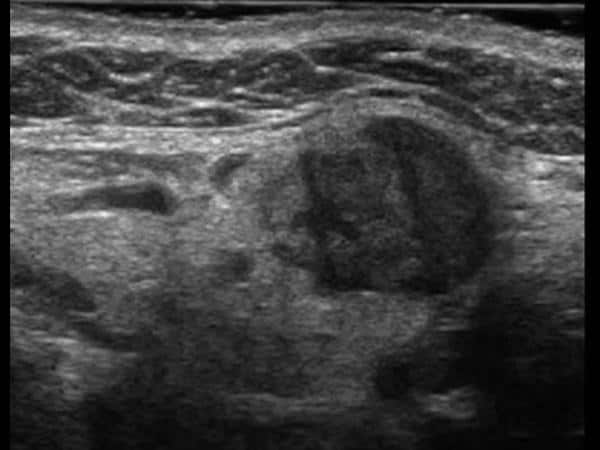

U tuyến nước bọt

» Thông tin: Nữ giới – 60 tuổi.

» Lâm sàng: Khối vùng góc hàm.

# Di căn tuyến nước bọt dưới hàm.